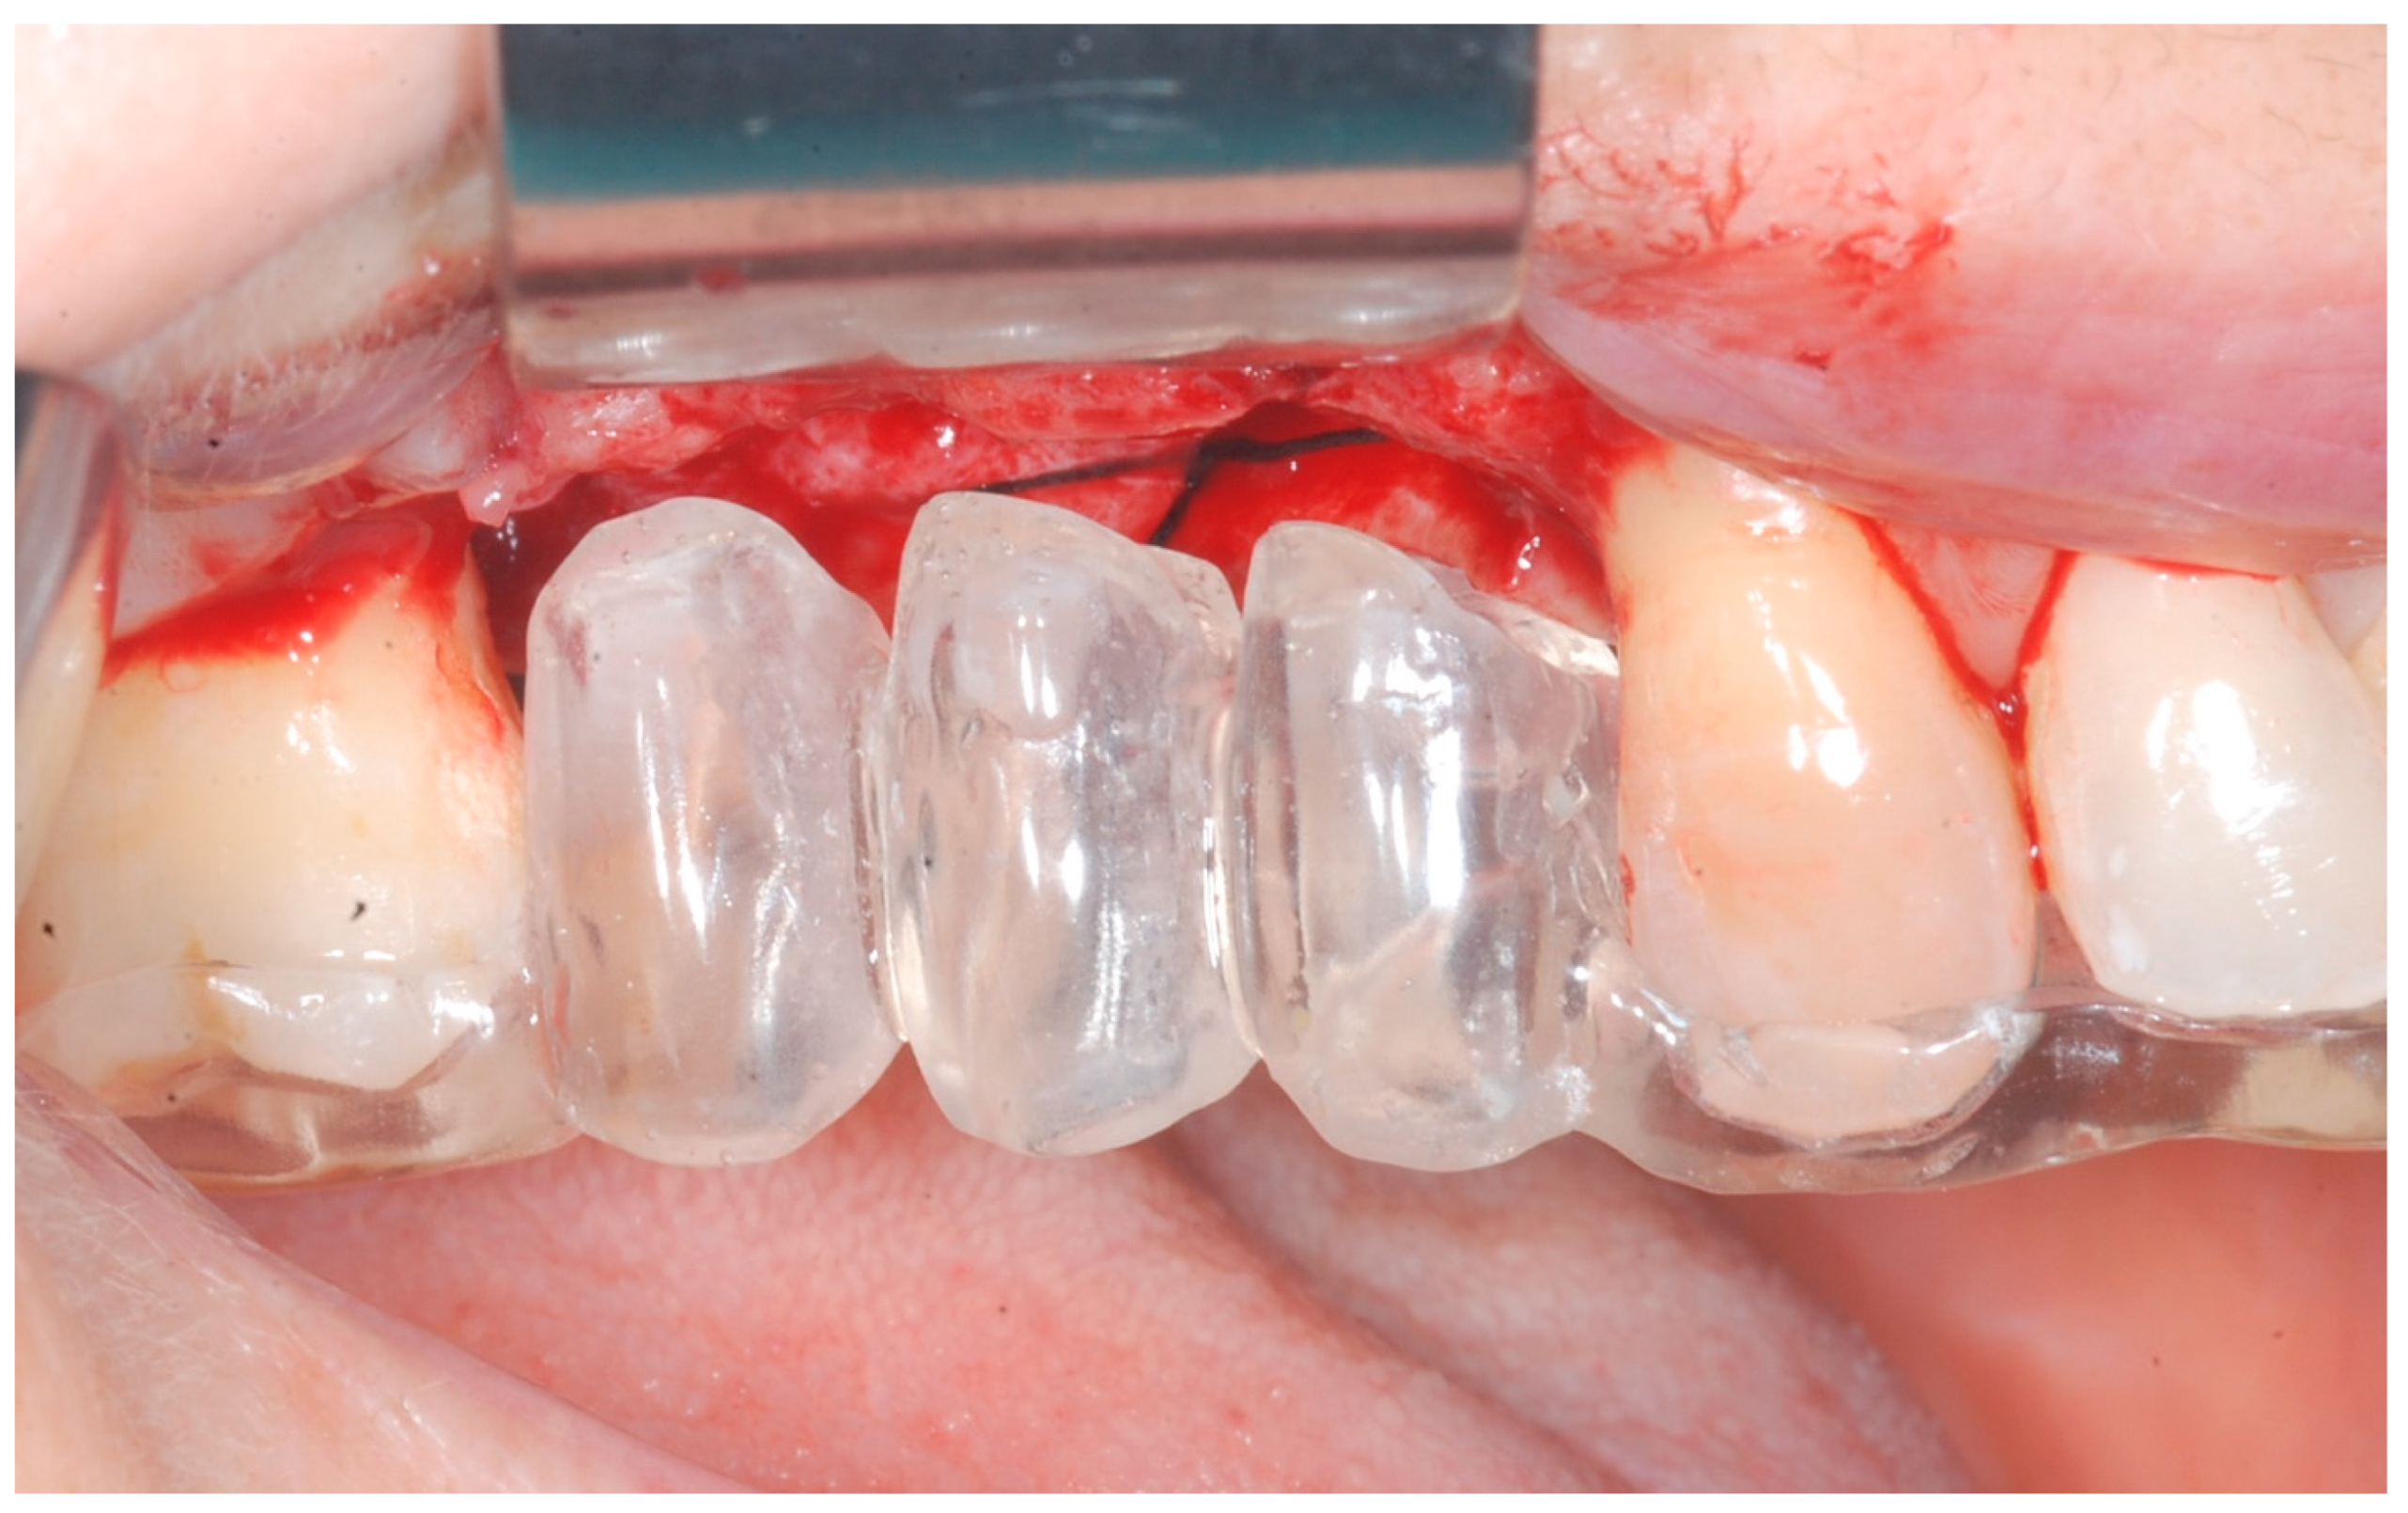

At this point, implants were placed according to the manufacturer’s instructions in a prosthetically ideal position with the aid of the surgical stent (Figure 3 and Figure 4).

Figure 3.

Surgical stent used for implant positioning.